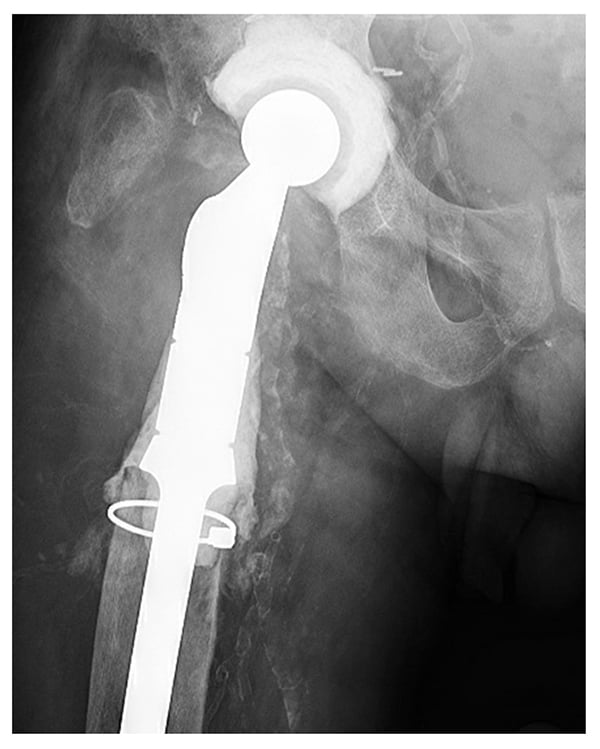

The patient underwent spacer removal, proximal femur resection, and proximal femoral spacer insertion. A Dall-Miles cable was placed around the proximal femur due to severe osteoporosis in this bony segment (Fig. 3). The patient once again was placed on limited weight bearing and IV antibiotics. After a 3-month antibiotic holiday, blood work and aspiration showed no infection. The patient then underwent reimplantation with a 68-mm multi-hole revision acetabular component. The ectatic, stovepipe femur precluded use of a modular tapered stem due to fracture concerns, and the history of recurrent infections precluded use of impaction grafting with cadaveric bone due to recurrent infection concerns.

Figure 3: Postoperative radiograph shows the revised articulating hip spacer with a proximal femoral replacement with a proximally coated stem with antibiotic cement. The acetabular component has been changed.